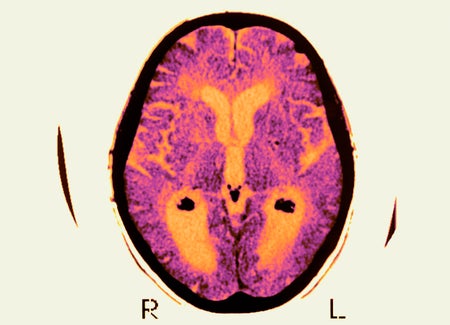

This Is Your Brain on Climate Change

Extreme heat caused by climate change can exacerbate a variety of neurological ailments, from Alzheimer’s disease to migraines to epilepsy, new research shows